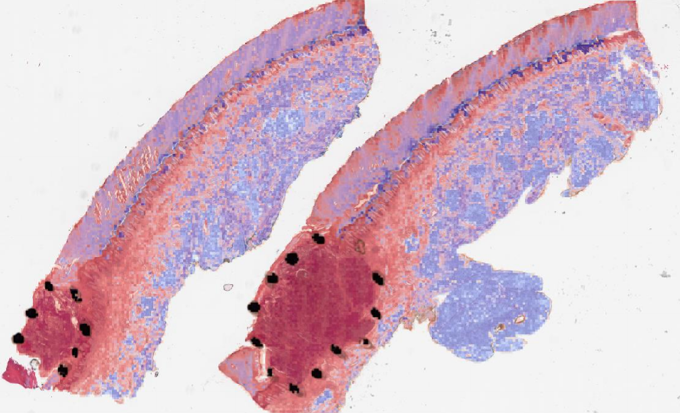

2.3 Model training and assessment

Training patch classifier. A three-class patch classification model (PCLA-3C) was trained on the labeled patches with VGG16 [31] as base architecture (Fig. 2d). Models were trained using this CNN architecture and by backpropagation, we manually changed the last layer’s parameters to optimize the model. The patch classifier would return a WSI with three key scores, corresponding to three categories (melanoma, nevus and other). Slide classification and ROI detection. In the testing stage, all patches from a WSI were first fed into the trained patch classifier. Ignoring patches predicted as other, slide-level prediction was done by majority vote based on patches predicted as melanoma and nevus. If the number of patches labeled as melanoma exceeded the number of patches labeled as nevus in one WSI, we classified it as melanoma, and vice versa (Fig. 2e). For a WSI classified as melanoma, all the patches from this slide will be ranked by melanoma predicted scores. Otherwise, all the patches will be ranked by nevus predicted scores (Fig. 2f). Model assessment. To evaluate the performance of ROI detection, the annotated ratio was measured to calculate Intersection over Union (IoU) for each slide. Given a slide, annotated ratio was calculated by the number of patches in the annotated region divided by the number of patches extracted from the slide: ,where is the number of patches in A (annotated region) and is the number of patches in C (WSI). Then, the top patches based on predicted scores were classified as ROI, where was the total number of patches from a slide. For example, if for a slide in the testing set, it means that 20% of the regions in the slide are ROIs. Then, the model will predict the top 20% of patches (based on the predicted scores) as patches in the ROIs. The performance was measured by Intersection over Union (IoU), which compared the annotated region and predicted ROI region. Since the framework was patch-based, IoU was calculated by the number of patches in the intersection region (the region in both annotated and predicted regions) divided by the number of patches in the union of the annotated and predicted ROI regions: , where shows the number of patches in the region of and shows the number of patches in the region of . A is annotated region and B is the predicted/highlighted region. Visualization. The detection methods could provide three types of visualization maps: boundary, overlap and heatmap (examples were in Fig. 3). Three visualization maps will be generated based on the predicted scores calculated in the ROI detection section (Fig. 2g). The overlap map highlighted top-ranked patches in a WSI and masks other areas with a transparent blue color (Fig. 3a, 3d). The percentage of highlighted patches equaled (the annotated ratio). Therefore, the highlighted region was also the predicted ROI. The boundary map showed the boundary of the largest ROI cluster based on the highlighted patches, where the highlighted patches were clustered by OPTICS algorithm [1] (Fig. 3b, 3e). The last one was a heatmap where red covered regions that had high predicted scores and blue covered regions that had low predicted scores (Fig. 3c, 3f).

(a) Boundary

(b) Overlay

(c) Heatmap

(d) Boundary

(e) Overlay

(f) Heatmap